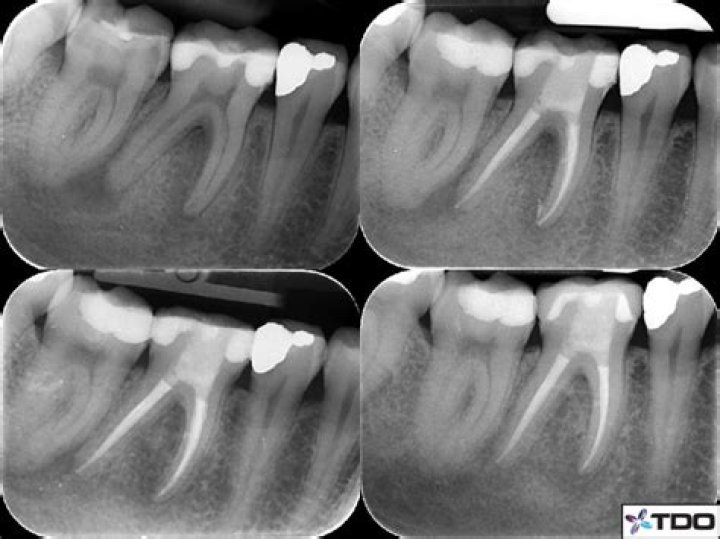

PARL stands for "Periapical Radiolucency".Click to see full answer. Similarly one may ask, what is PARL in dental?Background. Periapical radiolucency is the